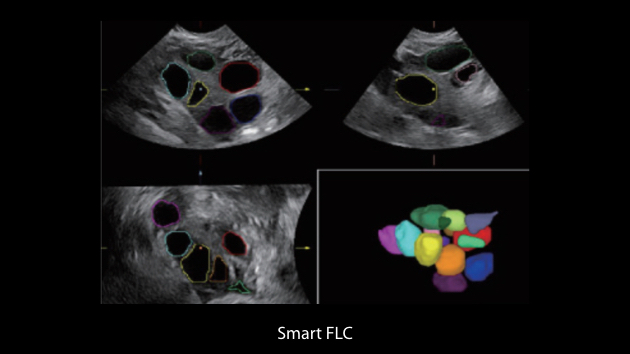

Le Nuewa?I9, con?u spÃĐcialement pour la santÃĐ de la femme et les soins nÃĐonataux, offre une expÃĐrience entiÃĻrement nouvelle gr?ce aux innovations dont il est dotÃĐ, tant à lâintÃĐrieur quâà lâextÃĐrieur. Ces innovations sont dÃĐveloppÃĐes sur la base d'une comprÃĐhension approfondie de scÃĐnarios cliniques complexes, fournissant des rÃĐponses prÃĐcises et adaptÃĐes ainsi qu'une efficacitÃĐ exceptionnelle et une expÃĐrience utilisateur remarquable.

La plate-forme ZST+?est une innovation extraordinaire, reprÃĐsentant une ÃĐvolution de lâimagerie ultrasonore. Elle transforme la formation conventionnelle de faisceaux en un traitement basÃĐ sur les canaux de donnÃĐes. Elle repousse les limites de lâimagerie conventionnelle et du compromis entre rÃĐsolution spatiale, rÃĐsolution temporelle et uniformitÃĐ tissulaire en offrant une qualitÃĐ dâimage exceptionnelle pour des solutions dâimagerie infinies et en constante ÃĐvolution.